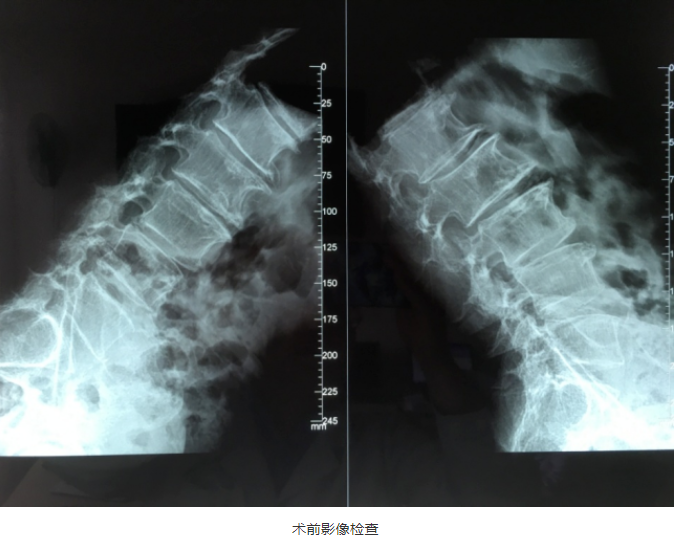

“OLIF作为一种更加微创的椎间融合术,近几年在国内各大医院逐渐开展,获得越来越多临床医生的认可”桃春辉院长介绍,该手术经左下腹腹外斜肌、腹内斜肌、腹横肌的肌间隙进入腹膜外间隙,在左侧腰大肌和腹主动脉之间安放工作通道,可通过大血管间隙及腰大肌间入路进行手术,可明显减少手术创伤、缩短手术时间、减少术中出血、缩短住院时间及患者康复时间。